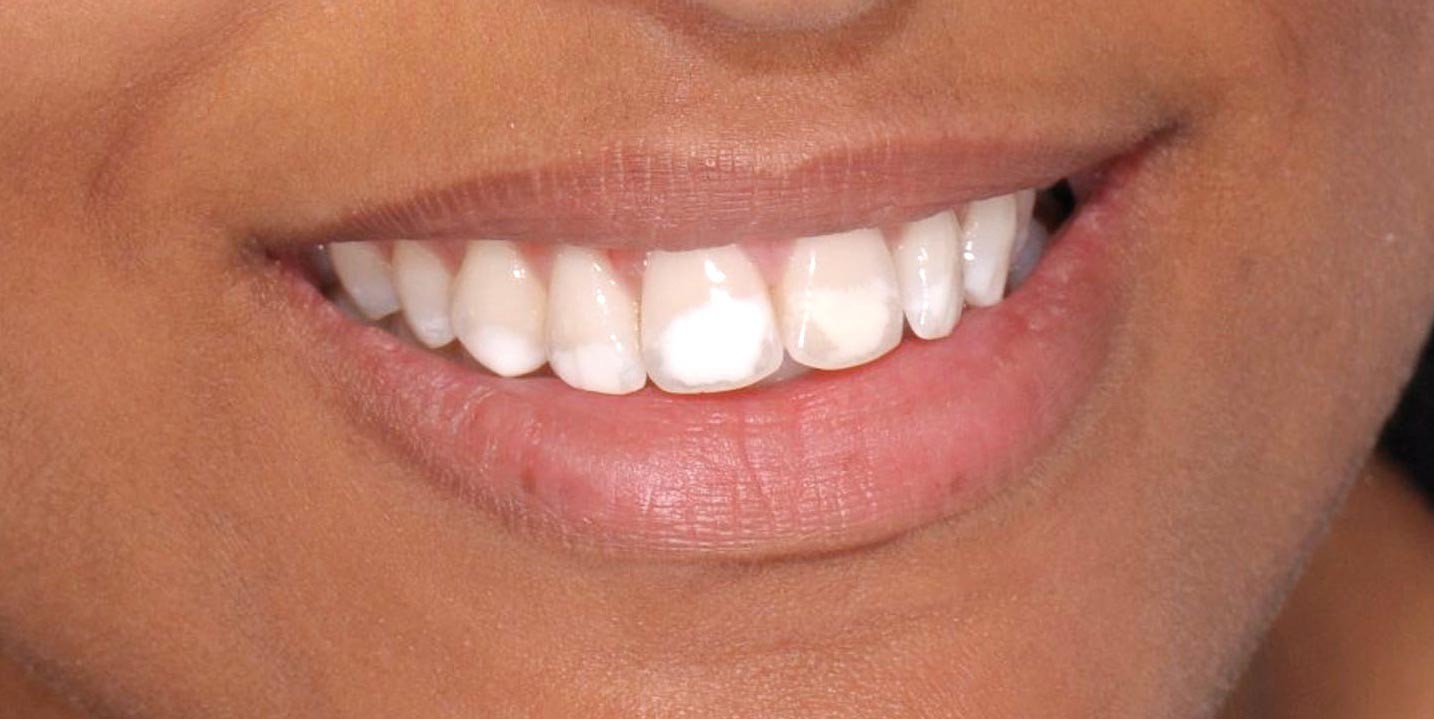

На фотографии зубы с нарушением эмали из-за недостаточного развития ее поверхностного слоя – гипоплазия.

Кариес в виде пятна следует отличать от таких заболеваний, как гипоплазия эмали и флюороз.